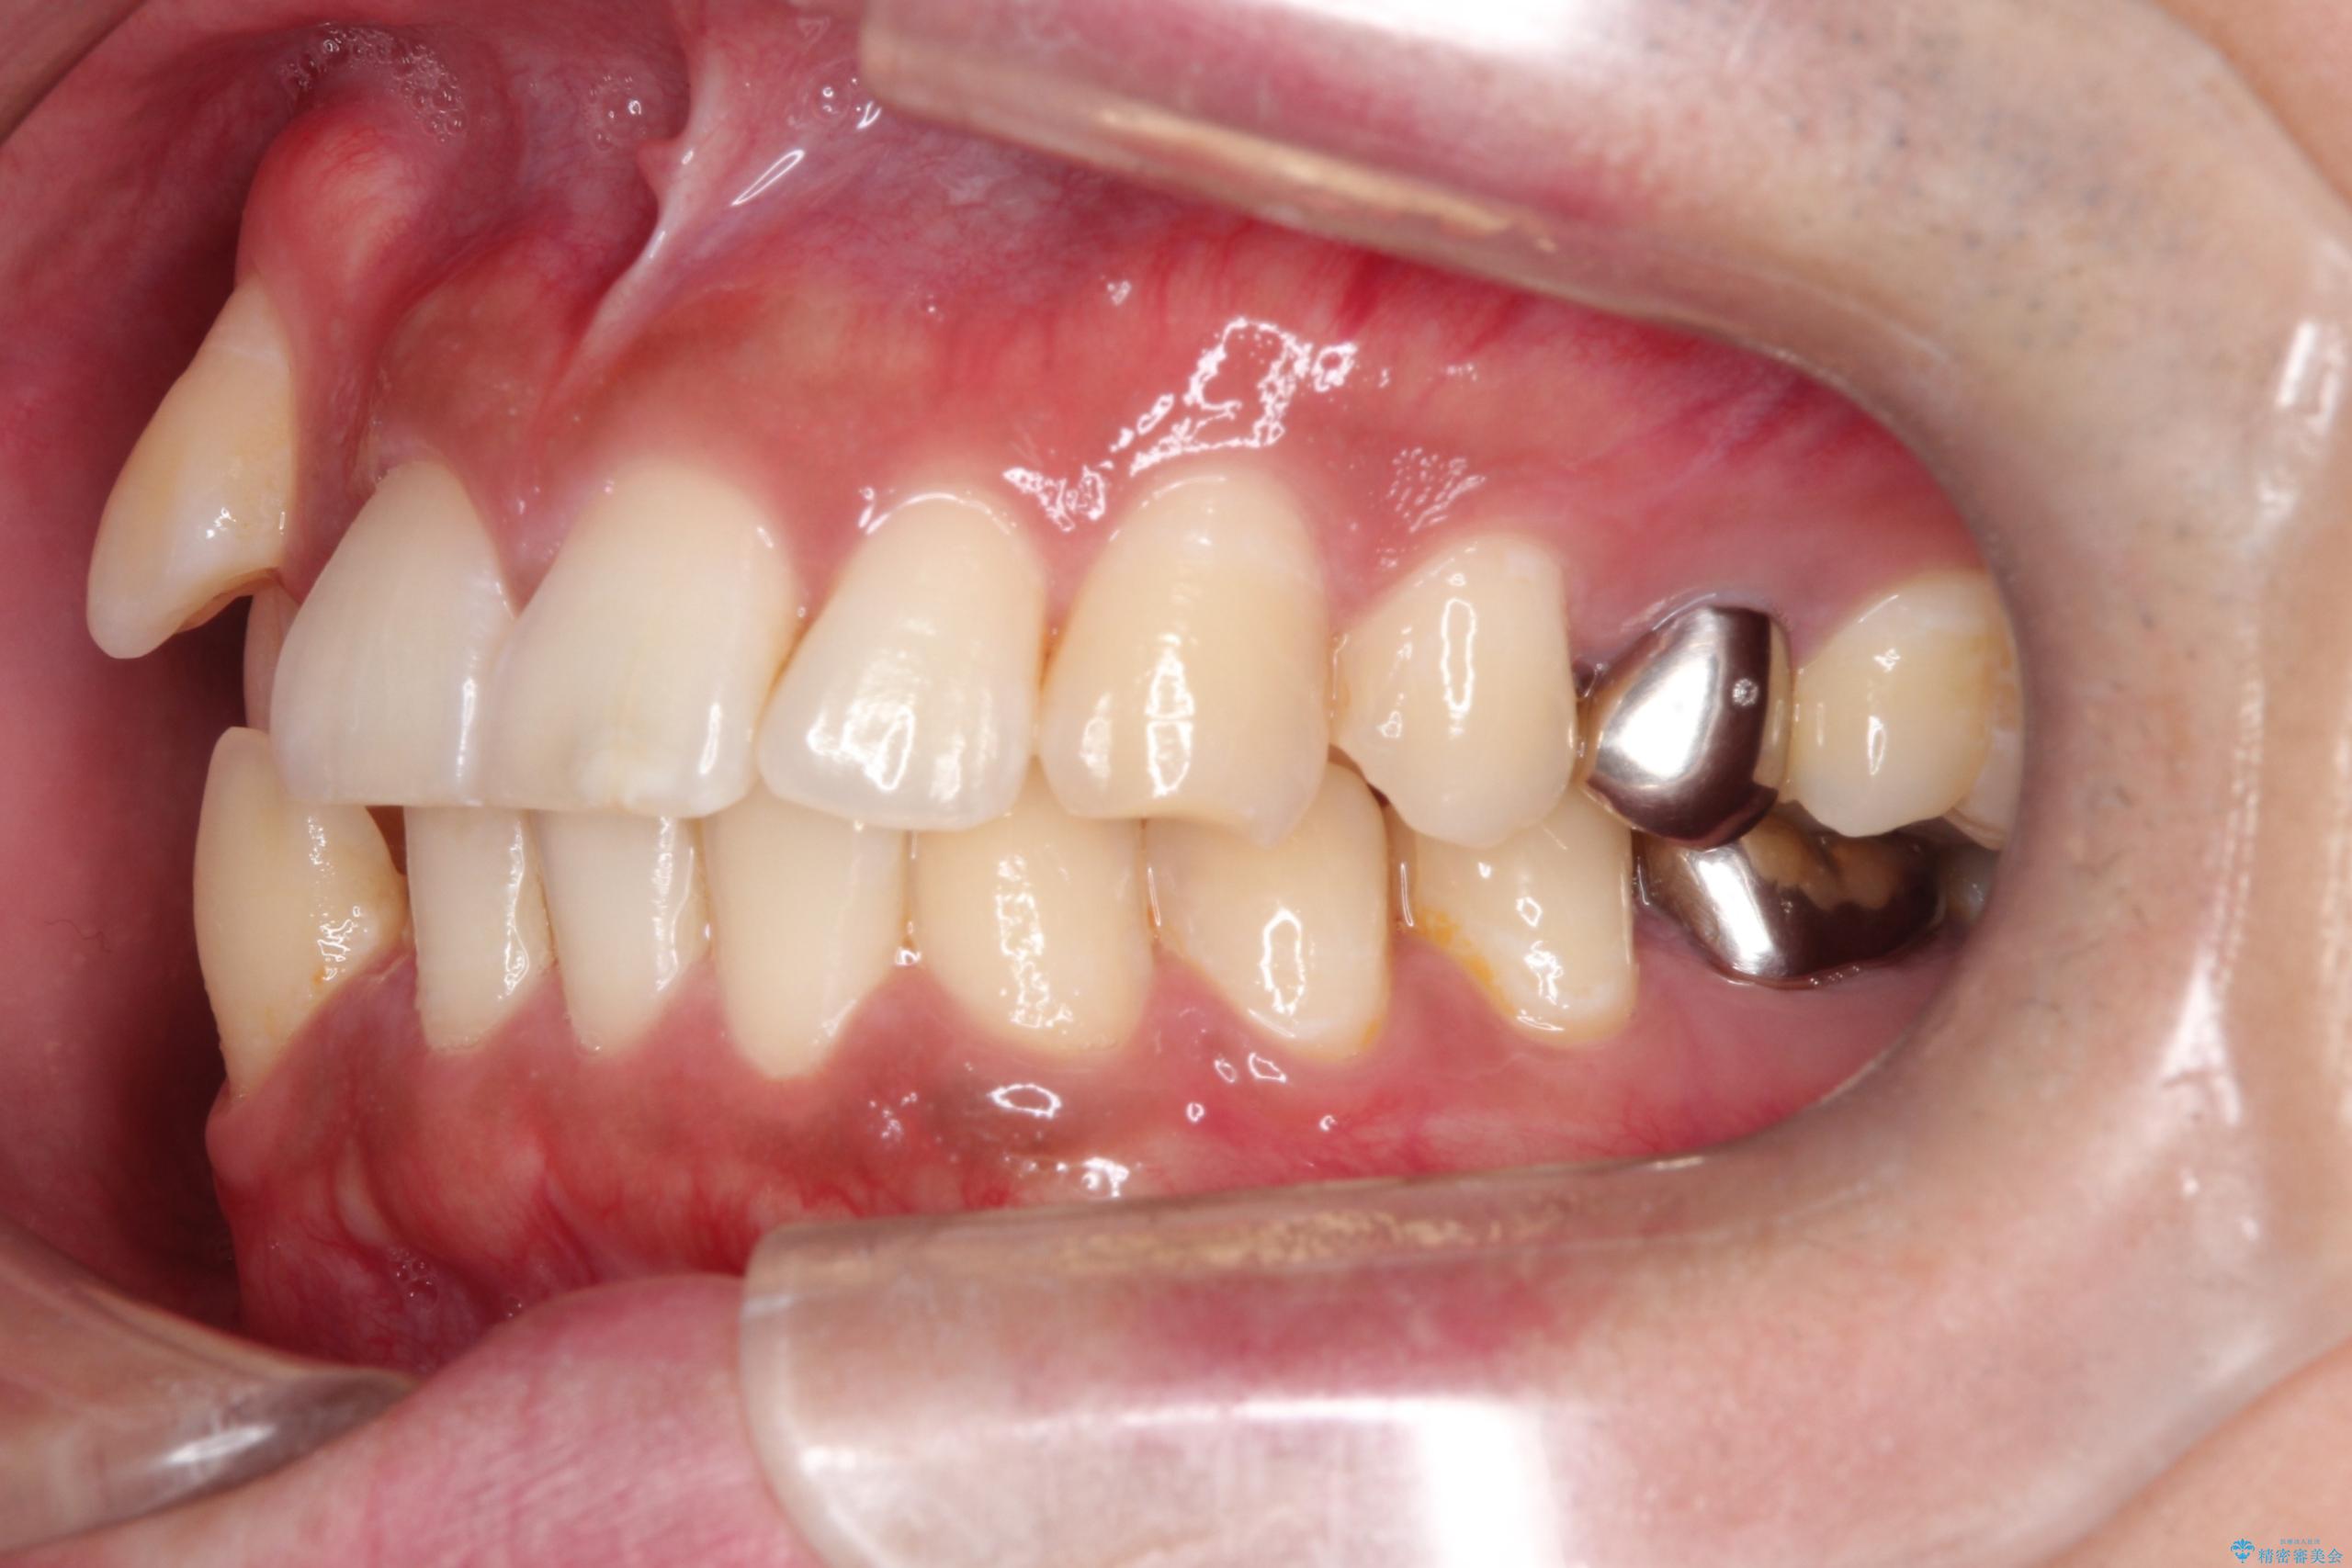

【ワイヤー矯正】八重歯と下の歯の凸凹を治したい

- 主訴:右上の八重歯と、下の歯の凸凹を治したい

上顎右側第一小臼歯と下顎右側第一小臼歯を抜歯しワイヤー矯正を行いました。

右側2級、左側1関係だったため、右側上下第一小臼歯を抜歯し、ワイヤー矯正を行いました。